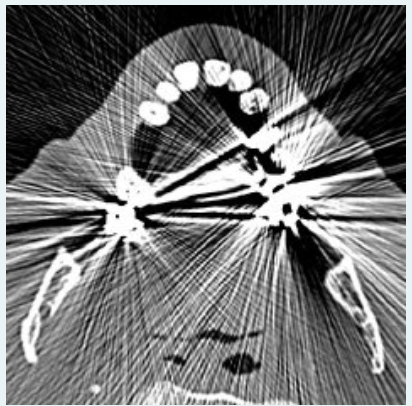

The streaking artifacts, depicted in the image below, is caused by:

a.metal dental fillings

b.detector malfunction

c.beam hardening

d.partial volume averaging

A